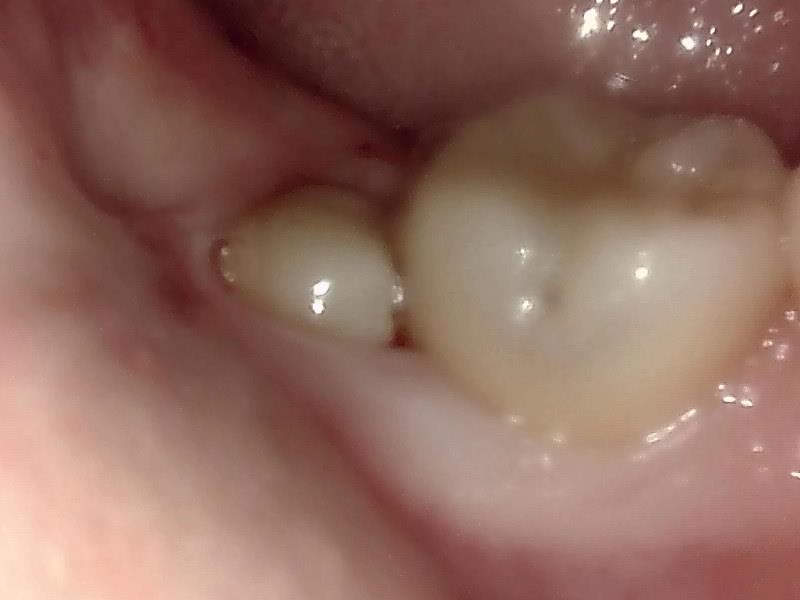

【Befor】

部位:右下8番埋伏歯

切開 歯肉剝離

歯肉を切開し、歯が見えるようにして、

周辺の骨を削らないように親知らずを分割し抜きやすくしていきます。

この抜歯法により術後の腫れ痛みが大幅に軽減されます。